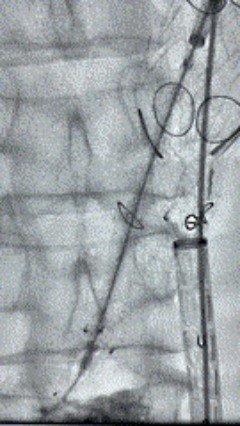

8. 从右侧股动脉入路送入腹主支架AB-24-12-110-S,近端重叠胸腹主动脉支架远端,调整好支架位置后释放。

9. 经左股动脉送入导丝导管,超选进腹主动脉支架短腿内,后沿导丝送入髂支,同理,右侧沿导丝送入髂支并释放,使用九州ku酷游顺应性球囊后扩各支架连接处及支架近远端,最后通过预留导管向瘤腔注入人纤维蛋白粘合剂数支,造影显示分支通畅。